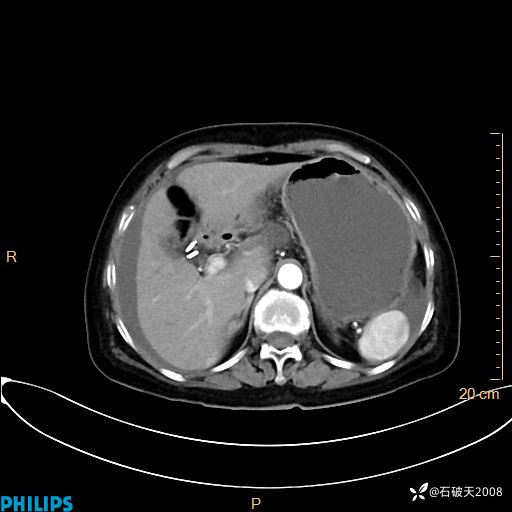

平扫